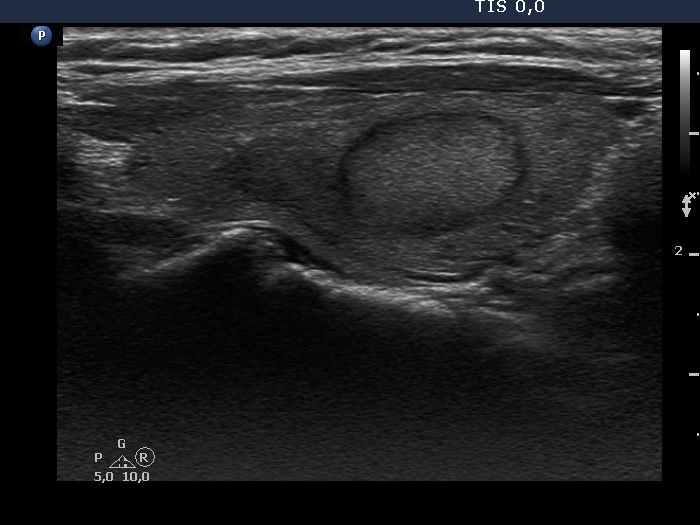

Discrete lesion or nodule in Hashimoto's thyroiditis - case 18 (99) (ultrasonographic picture 6)

Left lobe, another longitudinal view. Note the hypoechogenic area just above (left in the image) to the echonormal nodule.